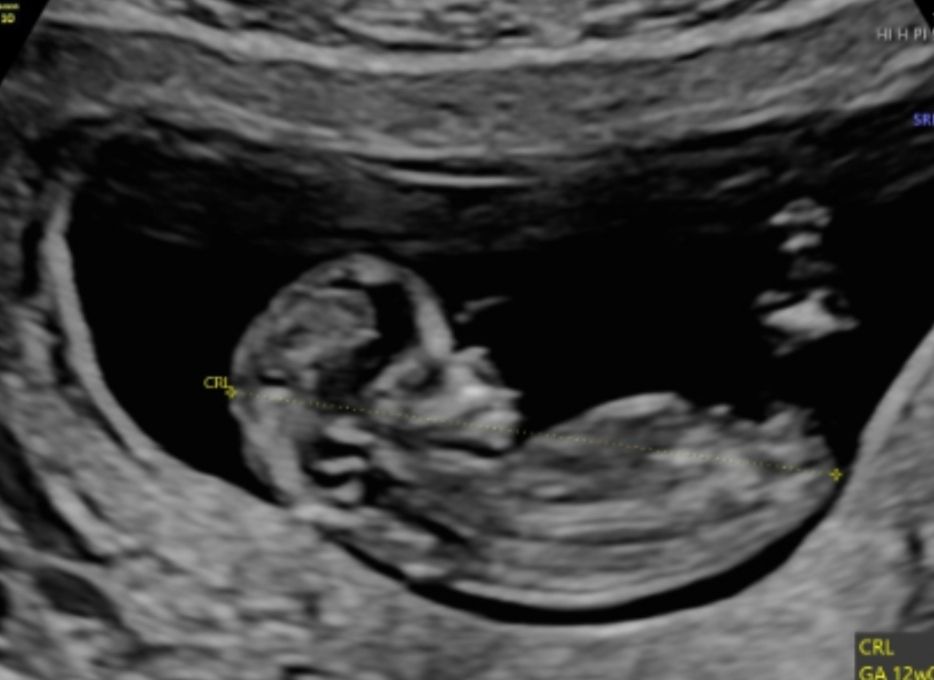

Первый скрининг ✅👌

11 недель 6 дней, видимо у меня начался токсикоз Соске быть!!!